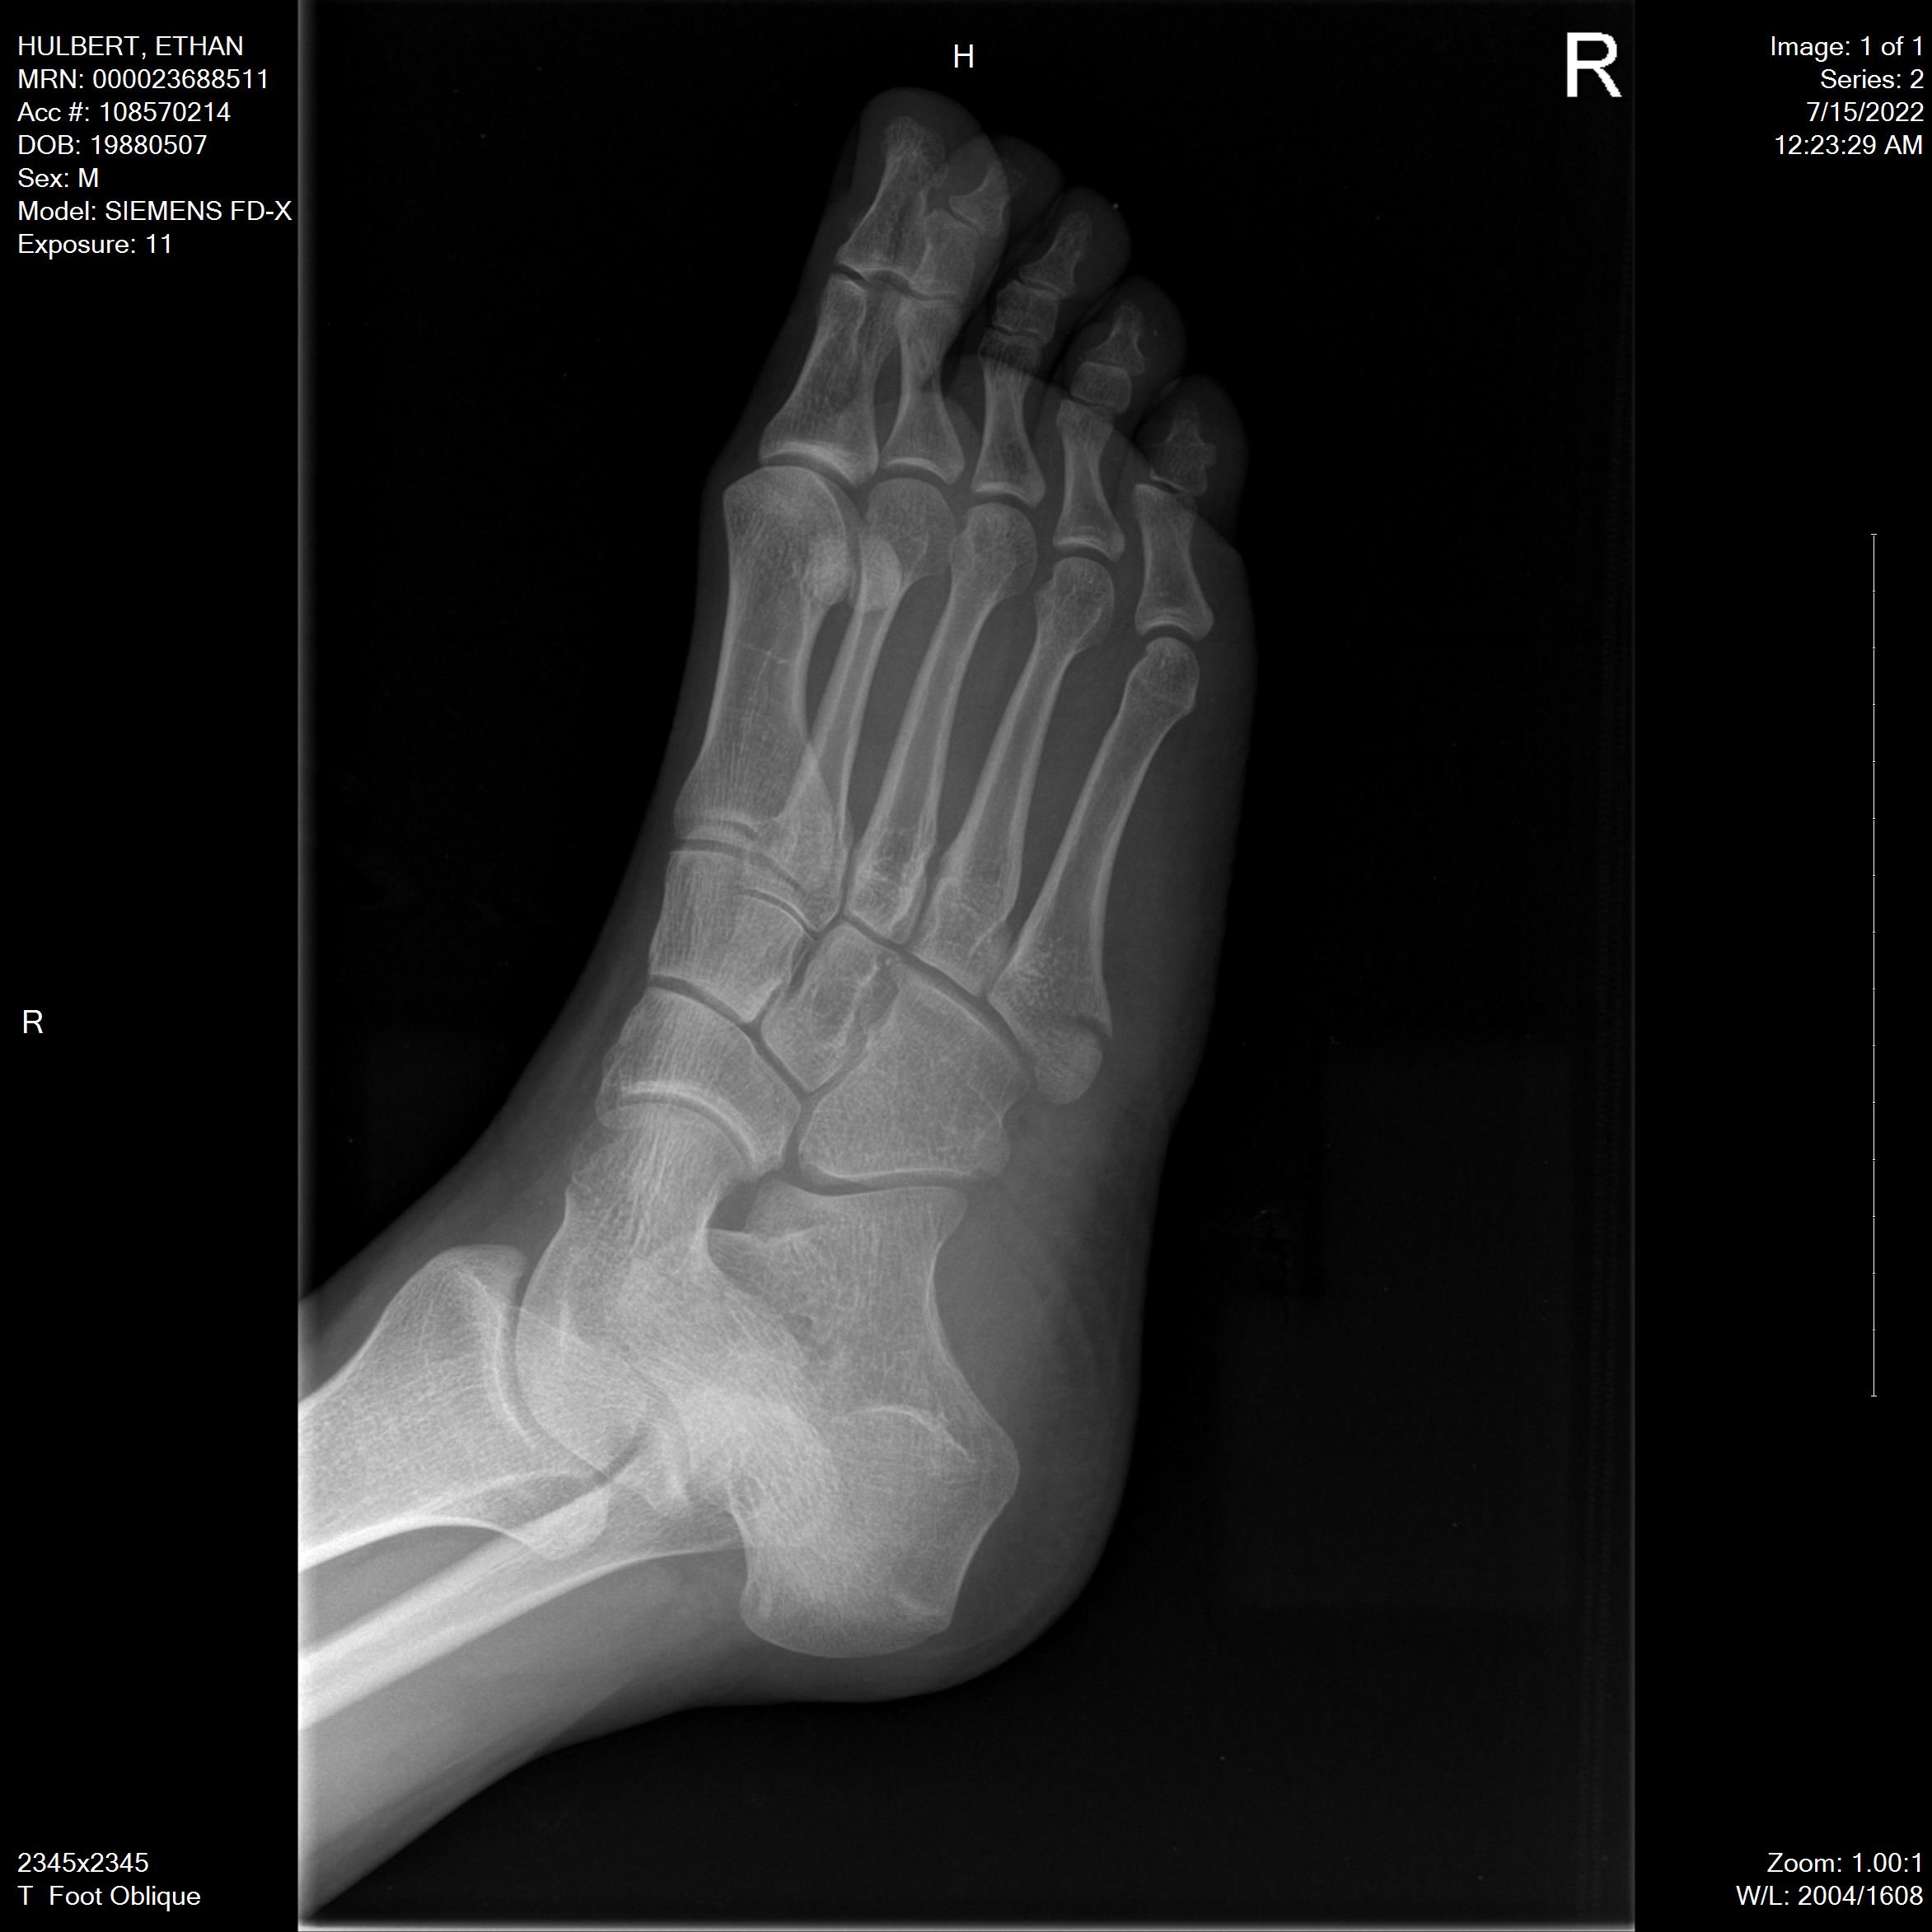

Right Foot: 2022 July

In July of 2022, I broke my right foot. I stepped over a curb wrong, twisted it, and when my weight went down on it, I’m lucky that the muscle didn’t break–instead, it was strong enough to pull one of my bones so hard it cracked it instead.

On the positive side, I got x-rays taken of my right foot from three different angles–the only useful thing Kaiser managed to do.

This software was fantastic. It let me see each x-ray in 7 different view modes, with different settings for brightness, contrast, color, and more. These different view modes are great for examining bones!

For each angle of my foot, I’ll show you the “reset” view (the default), the “auto” view (lower contrast), the “hot metal” view (molten orange–like I’m a fire elemental), three different “rainbow” modes (rainbow default, rainbow16, and rainbow65, whatever that means), and finally the “Bronson” mode. I have no idea what Bronson means.

Oblique Angle

Black and White “Reset” Default View: